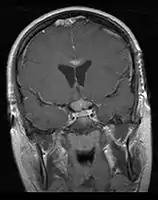

- Mainly located in midline structures, suprasellar region or pineal gland, also basal ganglia and hypothalamus

- Pineal Gland Germinoma

- Suprasellar Germinoma

- Whole ventricular volume: 3rd, 4th, lateral, prepontine cistern